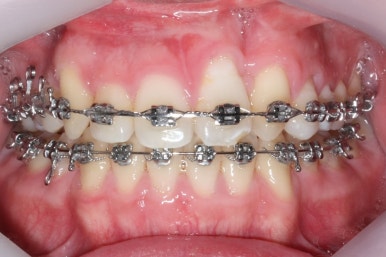

가장 최근의 사진입니다.

아직 치료 종료는 안되었으나 약간의 조절을 더하면 치료를 마무리할 수 있을 것 같습니다.

물론 윗니 한 쪽은 작은 앞니가 없고 한 쪽은 작은 어금니가 없기 때문에 중앙선이 100% 일치하지는 못하겠지만 기능적으로나 미적으로나 매우 개선되었음은 틀림없습니다.

치료 전과 가장 최근의 사진을 비교해 보겠습니다.

좌측이 부산구순구개열 전, 우측이 가장 최근의 사진들입니다.

거꾸로 물리던 앞니가 개선되었습니다.

좁아져 있고 찌그러진 위턱뼈의 형태가 개선되었습니다.

영구치 개수가 모자라는 선천결손이 있었지만 아랫니도 개수를 맞춰줌으로써 치아의 맞물림도 상당히 좋아졌습니다.